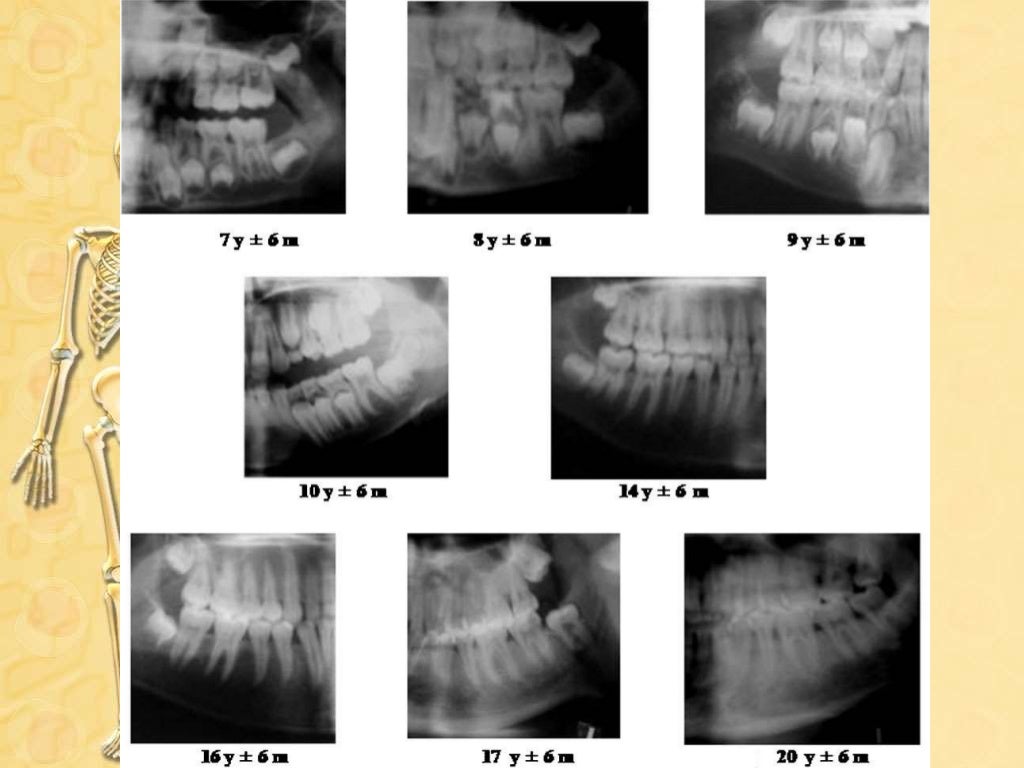

Role Of Radiology In Forensic Odontology Ppt . Radiography can play an important part in forensic odontology, mainly to establish identification. Forensic odontology is a unique field that combines the skills of a specially trained dentist with those of law enforcement. Forensic odontology is a branch of forensic medicine which, in the interest of justice, deals with the. Here's an introduction to the field of forensic odontology; This document provides an overview of forensic odontology, which involves the examination and analysis of dental evidence for use in legal investigations and. A summary of the type of cases where the expertise of an odontologist is required.